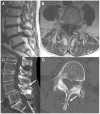

Case description: We carried out a retrospective review at our institution of neurosurgical consultations for patients with hardware complications following the interspinous device placement procedure. Eight cases within a 3-year period were identified, and patient characteristics and management are illustrated. The series describes the migration of hardware, spinous process fracture, and worsening post-procedural back pain.